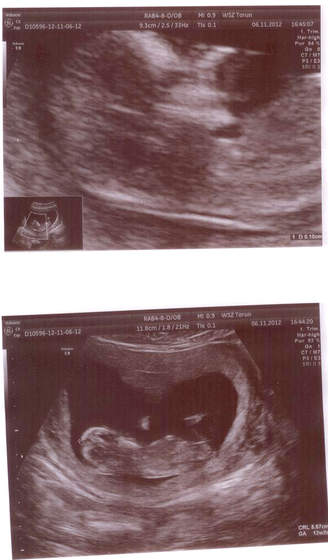

Znalazłam fajny artykuł o rozpoznawaniu płci. Jak przewiniecie troszkę w dół stronę, to będą dwa zdjęcia porównawcze